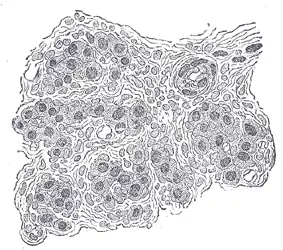

![]() Diagram showing the origins of the main branches of the carotid arteries. | |

The carotid body is situated on the posterior aspect of the bifurcation of the common carotid artery.[3]